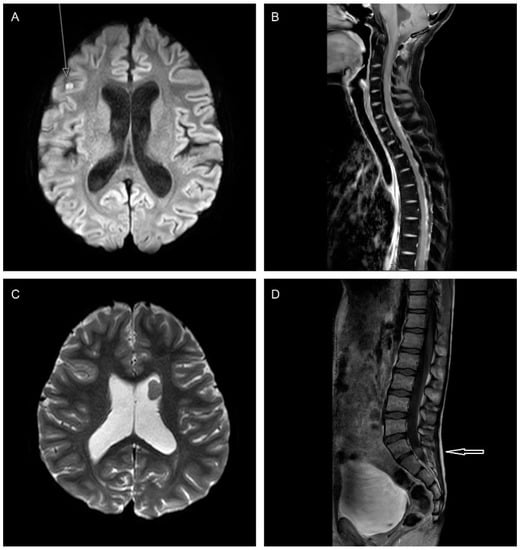

3.2. Staging: Neuro-Radiological Assessment

Response Assessment following Relapse